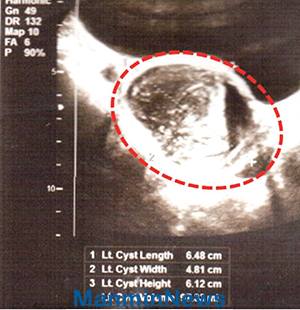

Ультразвуковой снимок

До молитвы: миома матки 6cm x 5cm

После молитвы: миома исчезла